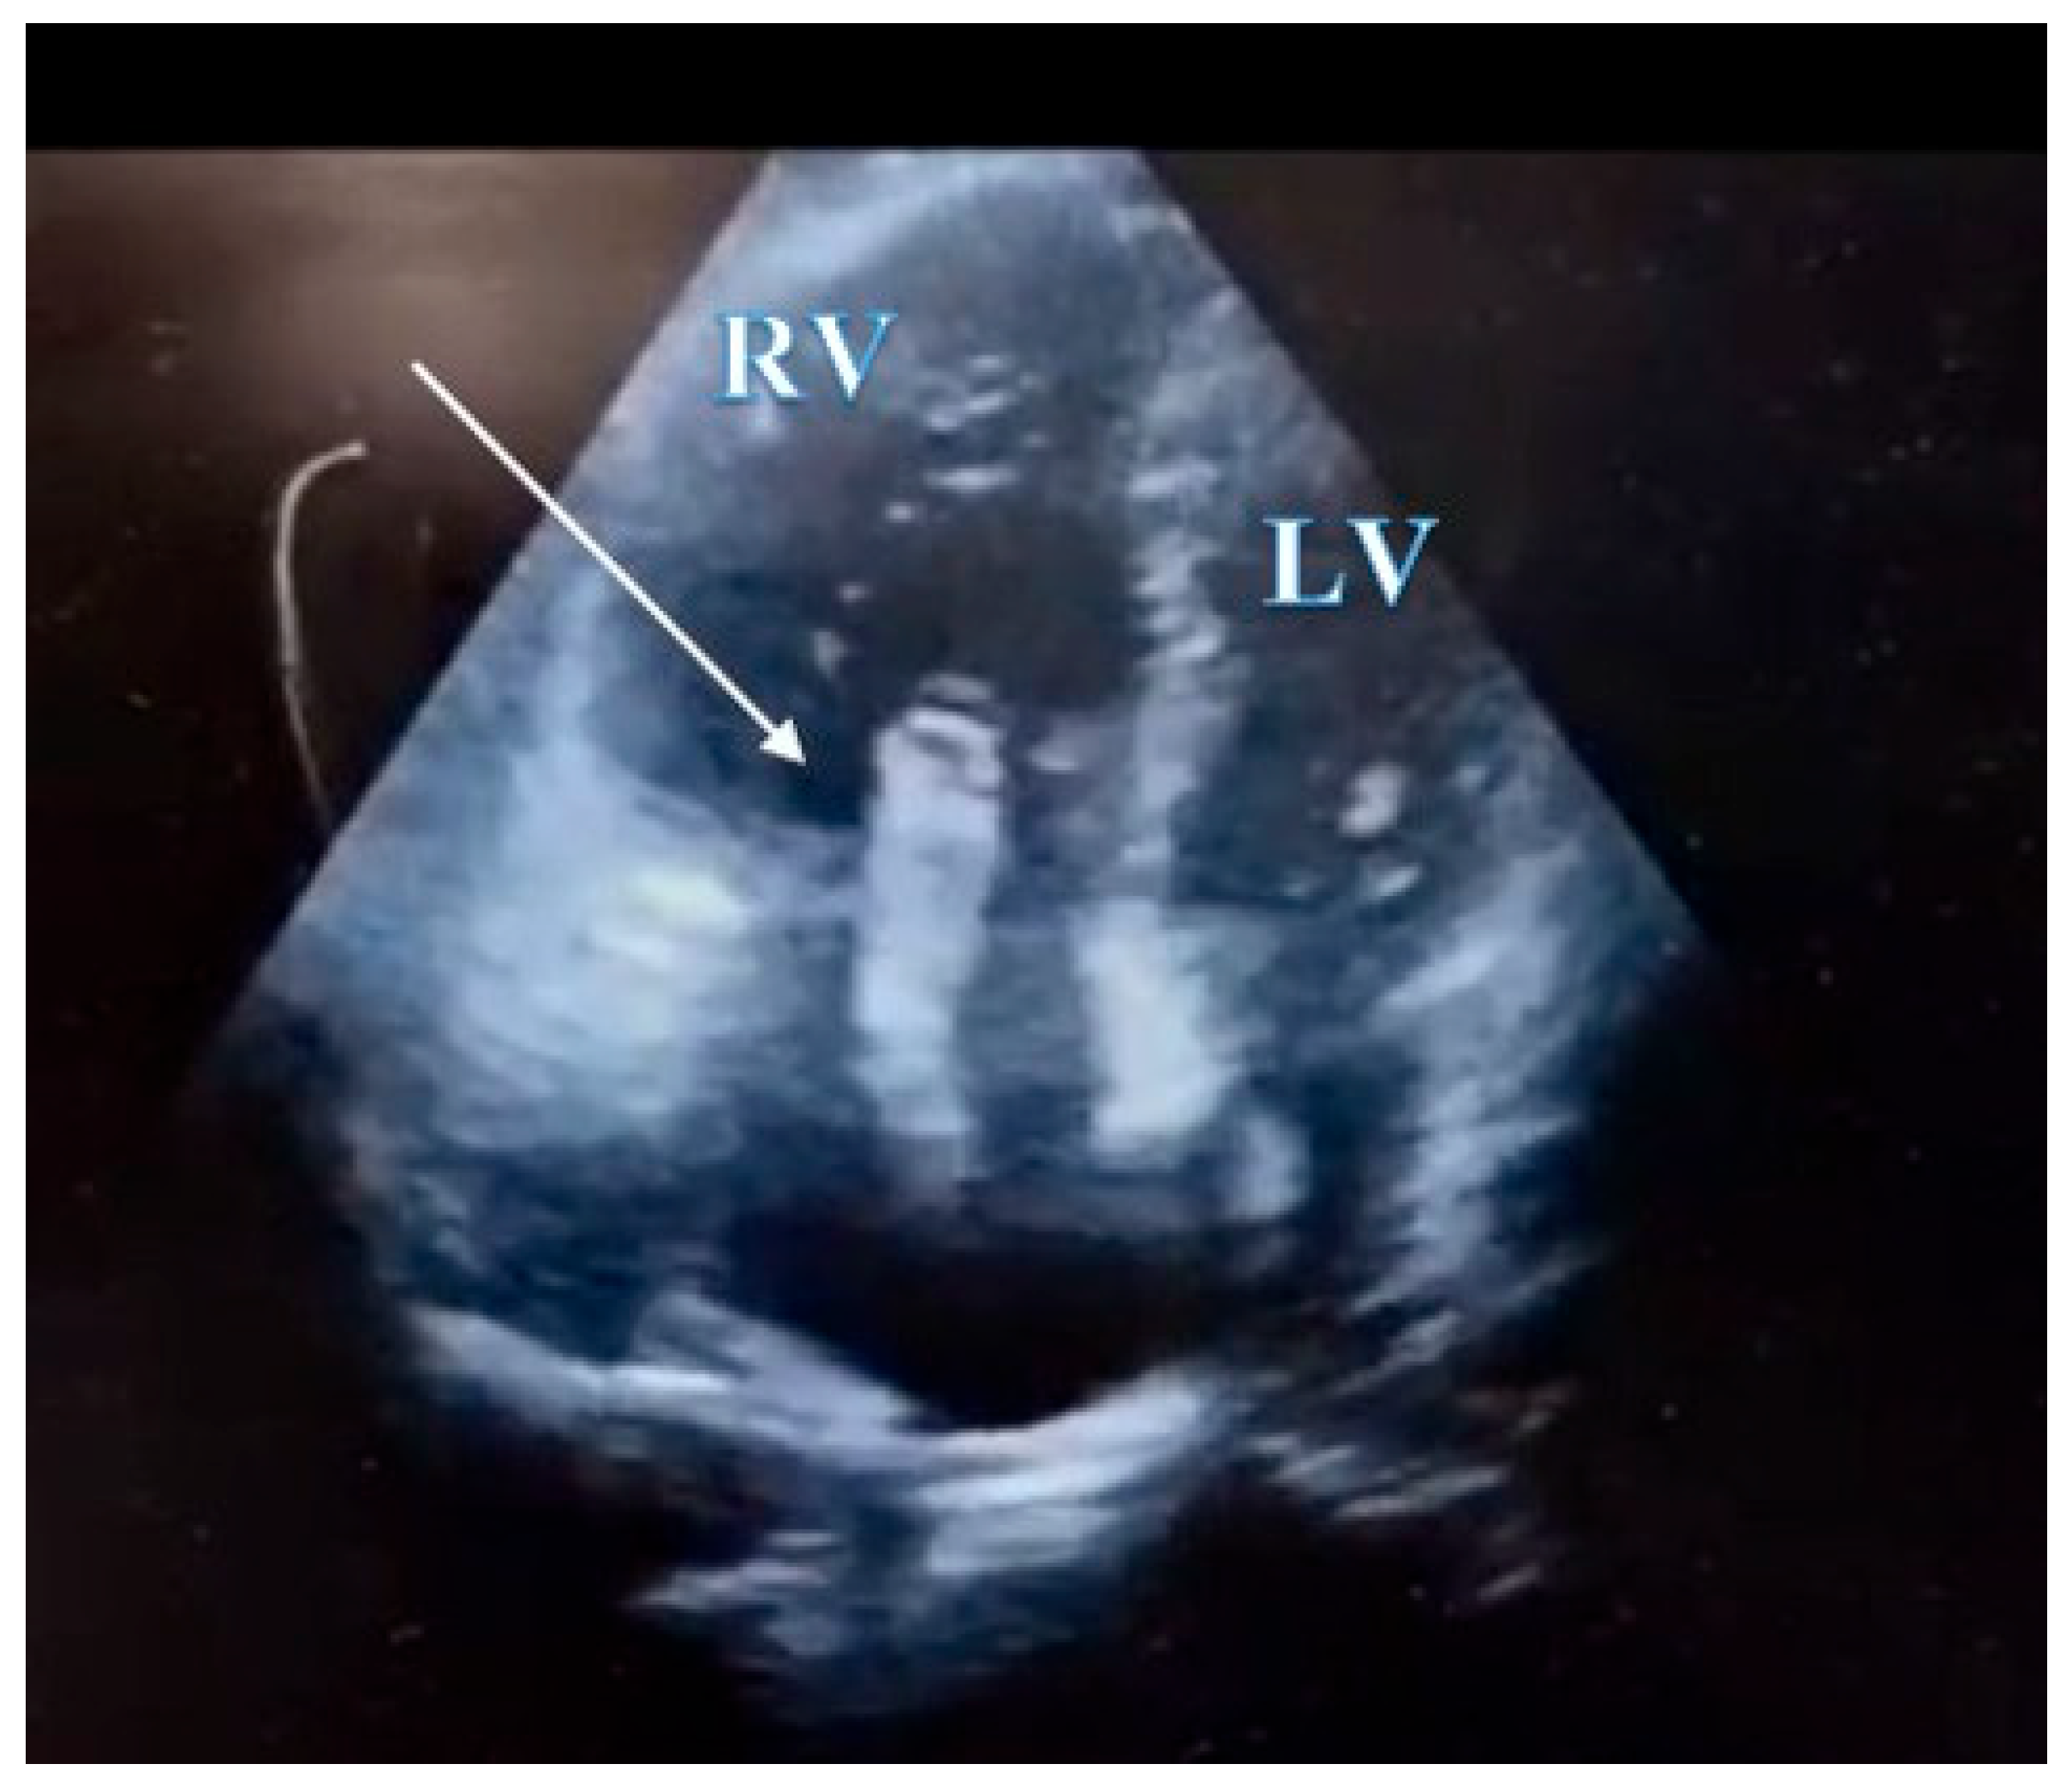

In the absence of any anamnestic or clinical evidence suggestive of pulmonary or myocardial infection (rapid influenza A/B and COVID-19 tests were also negative), acute myocardial infarction, or aortic dissection, and considering the laboratory findings, the clinical suspicion of pulmonary embolism became increasingly prominent, prompting the immediate performance of transthoracic echocardiography. Point-of-care transthoracic echocardiography (POCUS-TTE) confirmed the physiological impact of acute right ventricular strain (Figure 1A and Figure 1B), demonstrating severe right ventricular dilation (46 mm below the tricuspid annulus), markedly reduced systolic function (tricuspid annular plane systolic excursion, TAPSE = 12 mm), and paradoxical interventricular septal motion resulting in a “D-shaped” left ventricle - findings consistent with acute right ventricular pressure overload (RV/RA gradient = 40 mmHg) (Figure 2). Crucially, a large, highly mobile, serpentine thrombus was visualized within the right atrium, with its free-floating end prolapsing toward the tricuspid valve orifice. The concomitant presence of asymptomatic left popliteal deep vein thrombosis (DVT) was also documented, with the thrombus exhibiting a non-adherent proximal end and an unstable, mobile pattern, further supporting the diagnosis of massive pulmonary embolism.

Figure 1. A. POCUS-TTE pre-thrombolysis showing a markedly dilated right ventricular cavity. Parasternal long-axis view showing acute dilatation of the right ventricle and pulmonary annulus, resulting in incomplete coaptation of the pulmonary valve cusps secondary to an abrupt increase in pulmonary artery pressure.